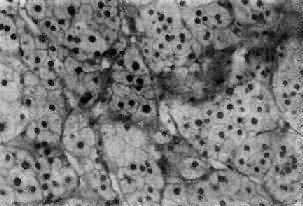

肾上腺皮质腺与局灶性结节性增生的病变相似,两者可以并发。腺通常是单侧单发性,并有薄层包膜,对周围组织有压迫现象,为鉴别的主要点。大小直径为1~5cm,切面黄色,有时呈红褐色,镜下多为类似束状带的泡沫状透明细胞,含有丰富类脂质,有时由类脂含量少的嗜酸性细胞构成,或者两种细胞混合存在。细胞排列成团,由含有毛细血管的少量间质分隔(图15-16)。部分腺为功能性,可引起醛固酮增多症或Cushing综合征,在形态上与非功能性腺没有区别。

图15-16 肾上腺皮质腺

上图 下图